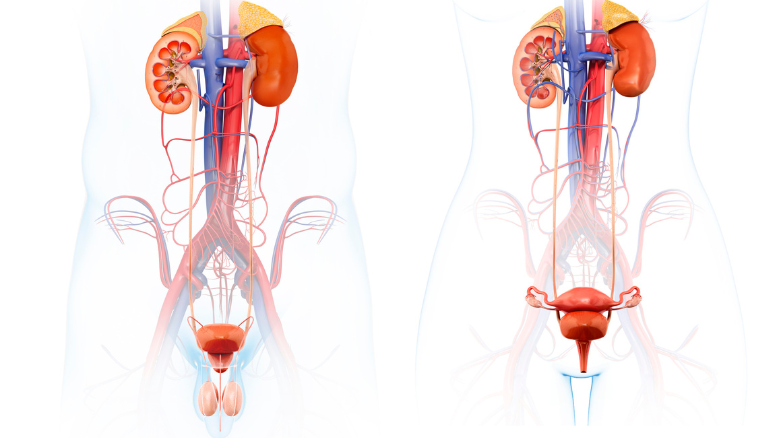

При лечении урологических заболеваний в медицинском центре «Альтернатива» применяется целостный подход по восстановлению всего организма: снижение веса, нормализации работы пищеварительного канала, восстановления работы печени, сосудов, лимфатической системы, восстановления обмена веществ, снижения массы тела. Проводится противопаразитарная, противовирусная терапия, восстановление позвоночника, очищение крови и лимфы.

Ультразвуковое исследование: УЗИ трансректальное органов малого таза у мужчин (предстательная железа, семенные мешочки, простатический отдел уретры, мочевой пузырь) + допплер; УЗИ мошонки; УЗИ + допплер сосудов верхних конечностей – ультразвуковое дуплексное сканирование вен рук; УЗИ + допплер сосудов нижних конечностей: ультразвуковое дуплексное сканирование вен ног.

Программа очищения организма является основной программой для восстановления работы всего организма и основой лечения урологических заболеваний, проводится в условиях стационара или амбулаторно на 5-10 дней. Программа очищения организма - дополнение к медикаментозной терапии.